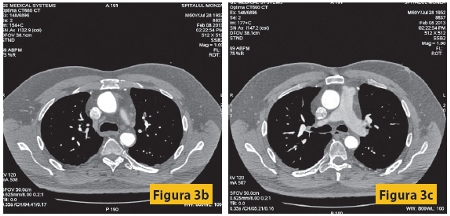

Figura 3: Pacient M, 60 ani, cunoscut cu by-pass aortocoronarian, cu dureri anginoase reapărute în ultimile 4 luni, cu multipli factori de risc cardio-vasculari: diabet zaharat, hipertensiune arterială, dislipidemie. Examinarea coronarografică nu poate preciza cu exactitate permeabilitatea graftului cu artera marginală stânga, care apare opacifiat, cel mai probabil prin umplere retrogradă.

La examenul angiocoronaro-CT se evidenţiază graft LIMA-LAD (artera marginală inferioară stângă - artera descendentă anterioară stângă) permeabil, GRAFT-AORTĂ-MARGINALĂ STÂNGA trombozat, VSI-AORTĂ-CORONARĂ DREAPTA bont închis la nivelul aortei, precum şi un stent patent la nivelul ramului intermediar.